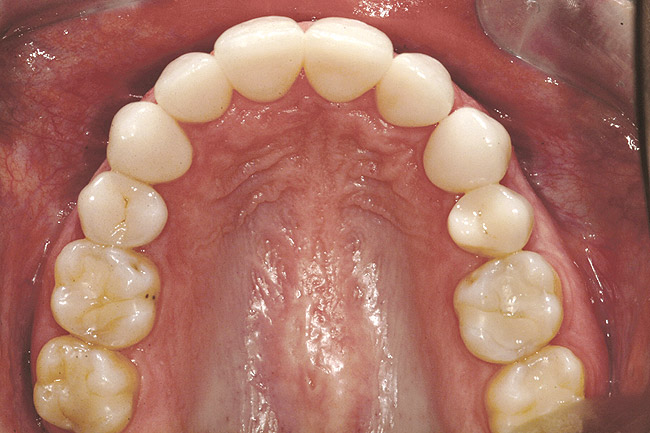

Fig 6 (and Fig 7). Prerestorative orthodontics was completed in 5 months. Final result 3 years, 4 months after completion.

Figure 6

Fig 7 (and Fig 6). Prerestorative orthodontics was completed in 5 months. Final result 3 years, 4 months after completion.

Figure 7

Fig 8 (and Fig 9). Teeth Nos. 5 and 12 were converted to Nos. 6 and 11, and Nos. 6 and 11 were converted to Nos. 7 and 10. Nos. 4 and 13 were enlarged. Note stability and absence of orthodontic relapse. Before-and-after smiles. Periodontist: Edward P. Allen, DDS, PhD. Prosthodontist: Robert R. Winter, DDS.

Figure 8

Fig 9 (and Fig 8). Teeth Nos. 5 and 12 were converted to Nos. 6 and 11, and Nos. 6 and 11 were converted to Nos. 7 and 10. Nos. 4 and 13 were enlarged. Note stability and absence of orthodontic relapse. Before-and-after smiles. Periodontist: Edward P. Allen, DDS, PhD. Prosthodontist: Robert R. Winter, DDS.

Figure 9